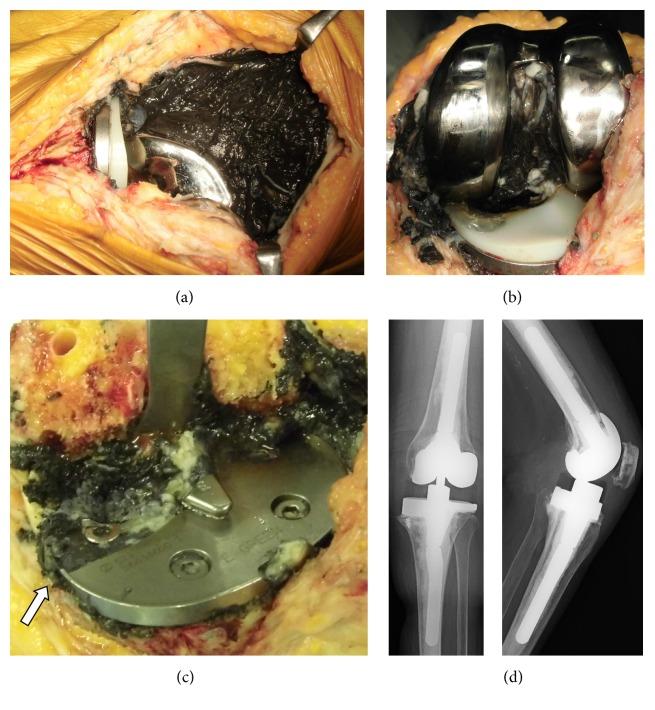

We report a rare case of tibial baseplate fracture of Miller-Galante II (MG II) prosthesis. We examine the factors that may cause such late fracture and review the literature on radiographic analysis and retrieval studies. A 76-year-old woman, who had undergone bilateral MG II total knee arthroplasty due to rheumatoid arthritis 16 years earlier, presented to our department with a 3-month history of left knee pain. Plain radiographs revealed severe distortion of the medial tibial component. During revision knee arthroplasty, we observed severe metallosis in the knee joint, polyethylene insert deformation, and posteromedial coronal baseplate fracture. After removal of the fractured tray, a bone deficit due to osteolysis was noted. The revision prosthesis (LCCK, Zimmer-Biomet) was implanted uneventfully. Four months after revision surgery, the patient was ambulating and had no complications. The implants on the right side had survived without complications for 17 years. We speculate that the primary causative factor of the fatigue fracture of the base plate due to loss of bony support most likely secondary to osteolysis was varus malalignment at primary implantation. This case highlights the importance of paying close attention to the correct alignment of each component at primary implantation.